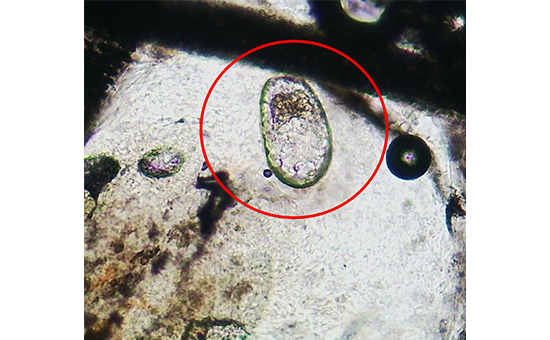

皮膚掻把検査(皮膚表層を削って顕微鏡で観察する)で虫体や虫卵を検出して診断します。しかし、掻痒感が強く発作を起こす可能性があるため、典型的な病変や症状から本疾患を疑い治療的診断として駆虫薬を投与する場合もあります。

モルモットの疥癬 (虫卵)